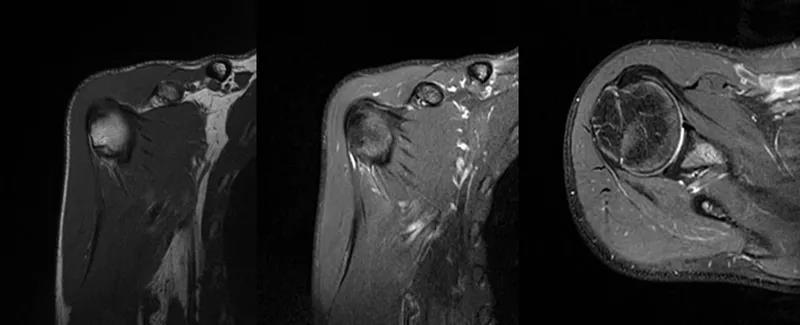

2、MRI检查MRI目前是诊断肩袖疾病中最常用的检查,可以直观的观察肩袖肌腱。

图21 斜冠状位(临床常用)a.T2,b.T1

图22 斜矢状位 a.冈上肌出口,肩袖诊断不如斜冠状位;b.冈上肌及肌腹脂肪浸润成度,评估手术与否

图23 横断位a.正常肩胛下肌;b.肩胛下肌损伤